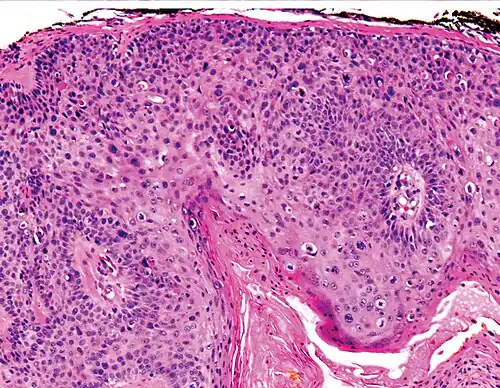

Histological characteristics

Histopathologically, the epidermis in cSCC in situ (Bowen's disease) will show hyperkeratosis and parakeratosis. There will also be marked acanthosis with elongation and thickening of the rete ridges. These changes will overly keratinocytic cells, which are often highly atypical and may have a more unusual appearance than invasive cSCC. The atypia spans the full thickness of the epidermis, with the keratinocytes demonstrating intense mitotic activity, pleomorphism, and greatly enlarged nuclei. They will also show a loss of maturity and polarity, giving the epidermis a disordered or "windblown" appearance.

Two types of multinucleated cells may be seen: the first will present as a multinucleated giant cell, and the second will appear as a dyskeratotic cell engulfed in the cytoplasm of a keratinocyte. Occasionally, cells of the upper epidermis will undergo vacuolization, demonstrating an abundant and strongly eosinophilic cytoplasm. There may be a mild to moderate lymphohistiocytic infiltrate detected in the upper dermis.[12]

Histopathology of squamous-cell carcinoma in situ (black arrow), compared to normal skin, showing marked atypia. -

Squamous-cell carcinoma in situ, showing prominent dyskeratosis and aberrant mitoses at all levels of the epidermis, along with marked parakeratosis.[12]